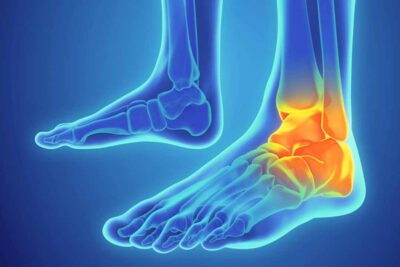

Chấn thương cổ chân là một trong những loại chấn thương phổ biến nhất trong lĩnh vực thể thao cũng như các hoạt động vận động hàng ngày. Không chỉ gây đau đớn, chấn thương này còn ảnh hưởng lớn đến sinh hoạt và khả năng vận động của người bị, thậm chí để lại các di chứng lâu dài nếu không được xử lý đúng cách. Việc hiểu rõ nguyên nhân, dấu hiệu nhận biết và cách xử lý đúng đắn sẽ giúp bạn hạn chế tối đa tác động của chấn thương cổ chân, đồng thời phục hồi nhanh chóng để trở lại hoạt động bình thường.

Dấu hiệu nhận biết chấn thương cổ chân

Khi bị chấn thương cổ chân, chúng ta thường có những phản ứng ban đầu rõ rệt giúp nhận biết rõ tình trạng tổn thương. Việc nhận biết sớm các dấu hiệu này không chỉ giúp xử lý kịp thời mà còn hạn chế các biến chứng nặng xảy ra về sau. Hiểu rõ các triệu chứng sẽ giúp bạn phân biệt chính xác hơn mức độ chấn thương và có hướng điều trị phù hợp.

Sưng đau, bầm tím và khó đứng hoặc đi lại

Khi cổ chân bị tổn thương, phản ứng ban đầu thường là sưng tấy do các mô mềm bị viêm, phù nề hoặc tích tụ máu sau va chạm. Cảm giác đau kéo dài hoặc tăng lên khi vận động sẽ gây cảm giác khó chịu rõ rệt, thậm chí mất khả năng đứng vững hoặc đi lại bình thường.

Bên cạnh sưng, nhiều trường hợp còn xuất hiện màu sắc bầm tím quanh vùng cổ chân do các mao mạch bị vỡ. Hiện tượng này thể hiện rõ mức độ tổn thương mô mềm, phản ánh rằng tổn thương đã ảnh hưởng sâu vào các cấu trúc bên trong. Người bị chấn thương thường cảm thấy vùng bị đau nhức dữ dội hoặc âm ỉ, và có thể đi kèm cảm giác tê liệt hoặc nóng rát, ảnh hưởng lớn tới khả năng vận động bình thường hàng ngày.